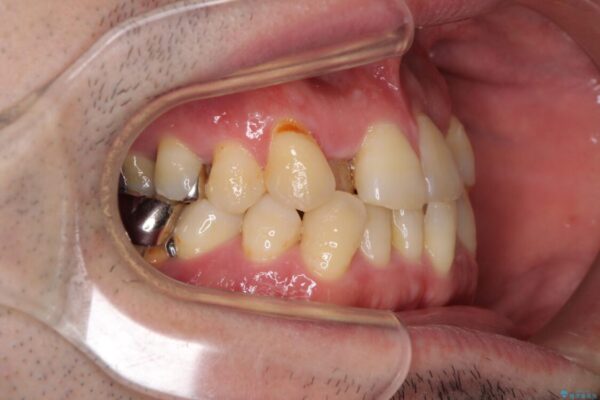

奥歯の痛みと前歯のデコボコを気にして来院された患者様です。

治療計画

左右下顎の大臼歯は、ともに歯根が破折しており、抜歯が必要な状態でした。

放置したことで炎症による骨吸収が顕著であるため、骨造成を併用してインプラント埋入を行うこととしました。

咬み合わせは受け口傾向であり、上顎前歯の叢生が顕著であったことから、第1小臼歯抜歯による矯正治療も検討しましたが、下顎大臼歯を左右ともに抜歯するため、非抜歯による矯正治療を行うこととしました。

治療前

• 割れてしまった奥歯とデコボコの前歯 矯正治療とインプラント治療 治療前画像